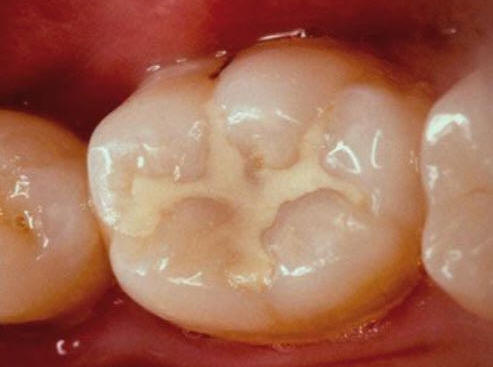

Una morfología de la fisura estrecha, con forma de botella de "Coca-Cola" genera un nicho ecológico ideal para la colonización de cualquier bacteria productora de ácidos. Al no poder remover en forma períodica dicho biofilm de una zona tan estrecha, el ataque ácido genera una lesión cariosa en la dentina, con un aspecto de esmalte intacto a la inspección visual, o sea un típico código 3 y 4 de ICDAS Completo. (Caries Moderada para el ICDAS COMBINADO)

Imagen digital que representa la microfiltración y penetración del sellante realizado.

Microfotografía: Muestra como el sellador obtura la caries subyascente, evitando su avance.

Código 3 (Caries moderada) in vitro. Los códigos 3 in vivo debe ser sellado para evitar el avance del proceso carioso. (MNO)

Código 4 (Caries moderada) in vitro. Los códigos 4 in vivo deben ser tratados en forma operatoria con preservación dental (MOPD), porque presentan dentina infectada.